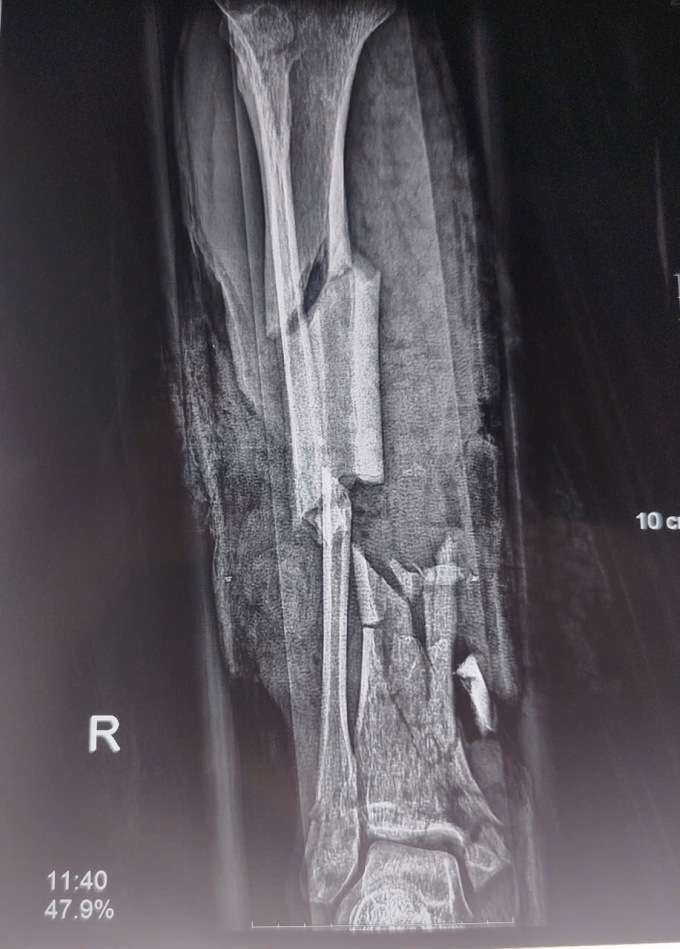

Ngày 21/1,ThS.BS Nguyễn Mộc Sơn,Khoa Phẫu thuật Chi trên và Y học Thể thao,Bệnh viện Việt Đức,cho biết bệnh nhân nhập viện với chấn thương nghiêm trọng: dập nát cẳng chân phải,gãy hở cẳng chân trái,vết thương phức tạp bàn tay hai bên,chấn thương bụng kín.

Do tổn thương nặng,bệnh nhân phải phẫu thuật cắt cụt 1/3 cẳng chân phải,sửa mỏm cụt ngón tay 4 và 5,đồng thời xử lý vết thương bàn tay hai bên.

Phim chụp chân tổn thương do nổ bình gas. Ảnh: Bệnh viện cung cấp